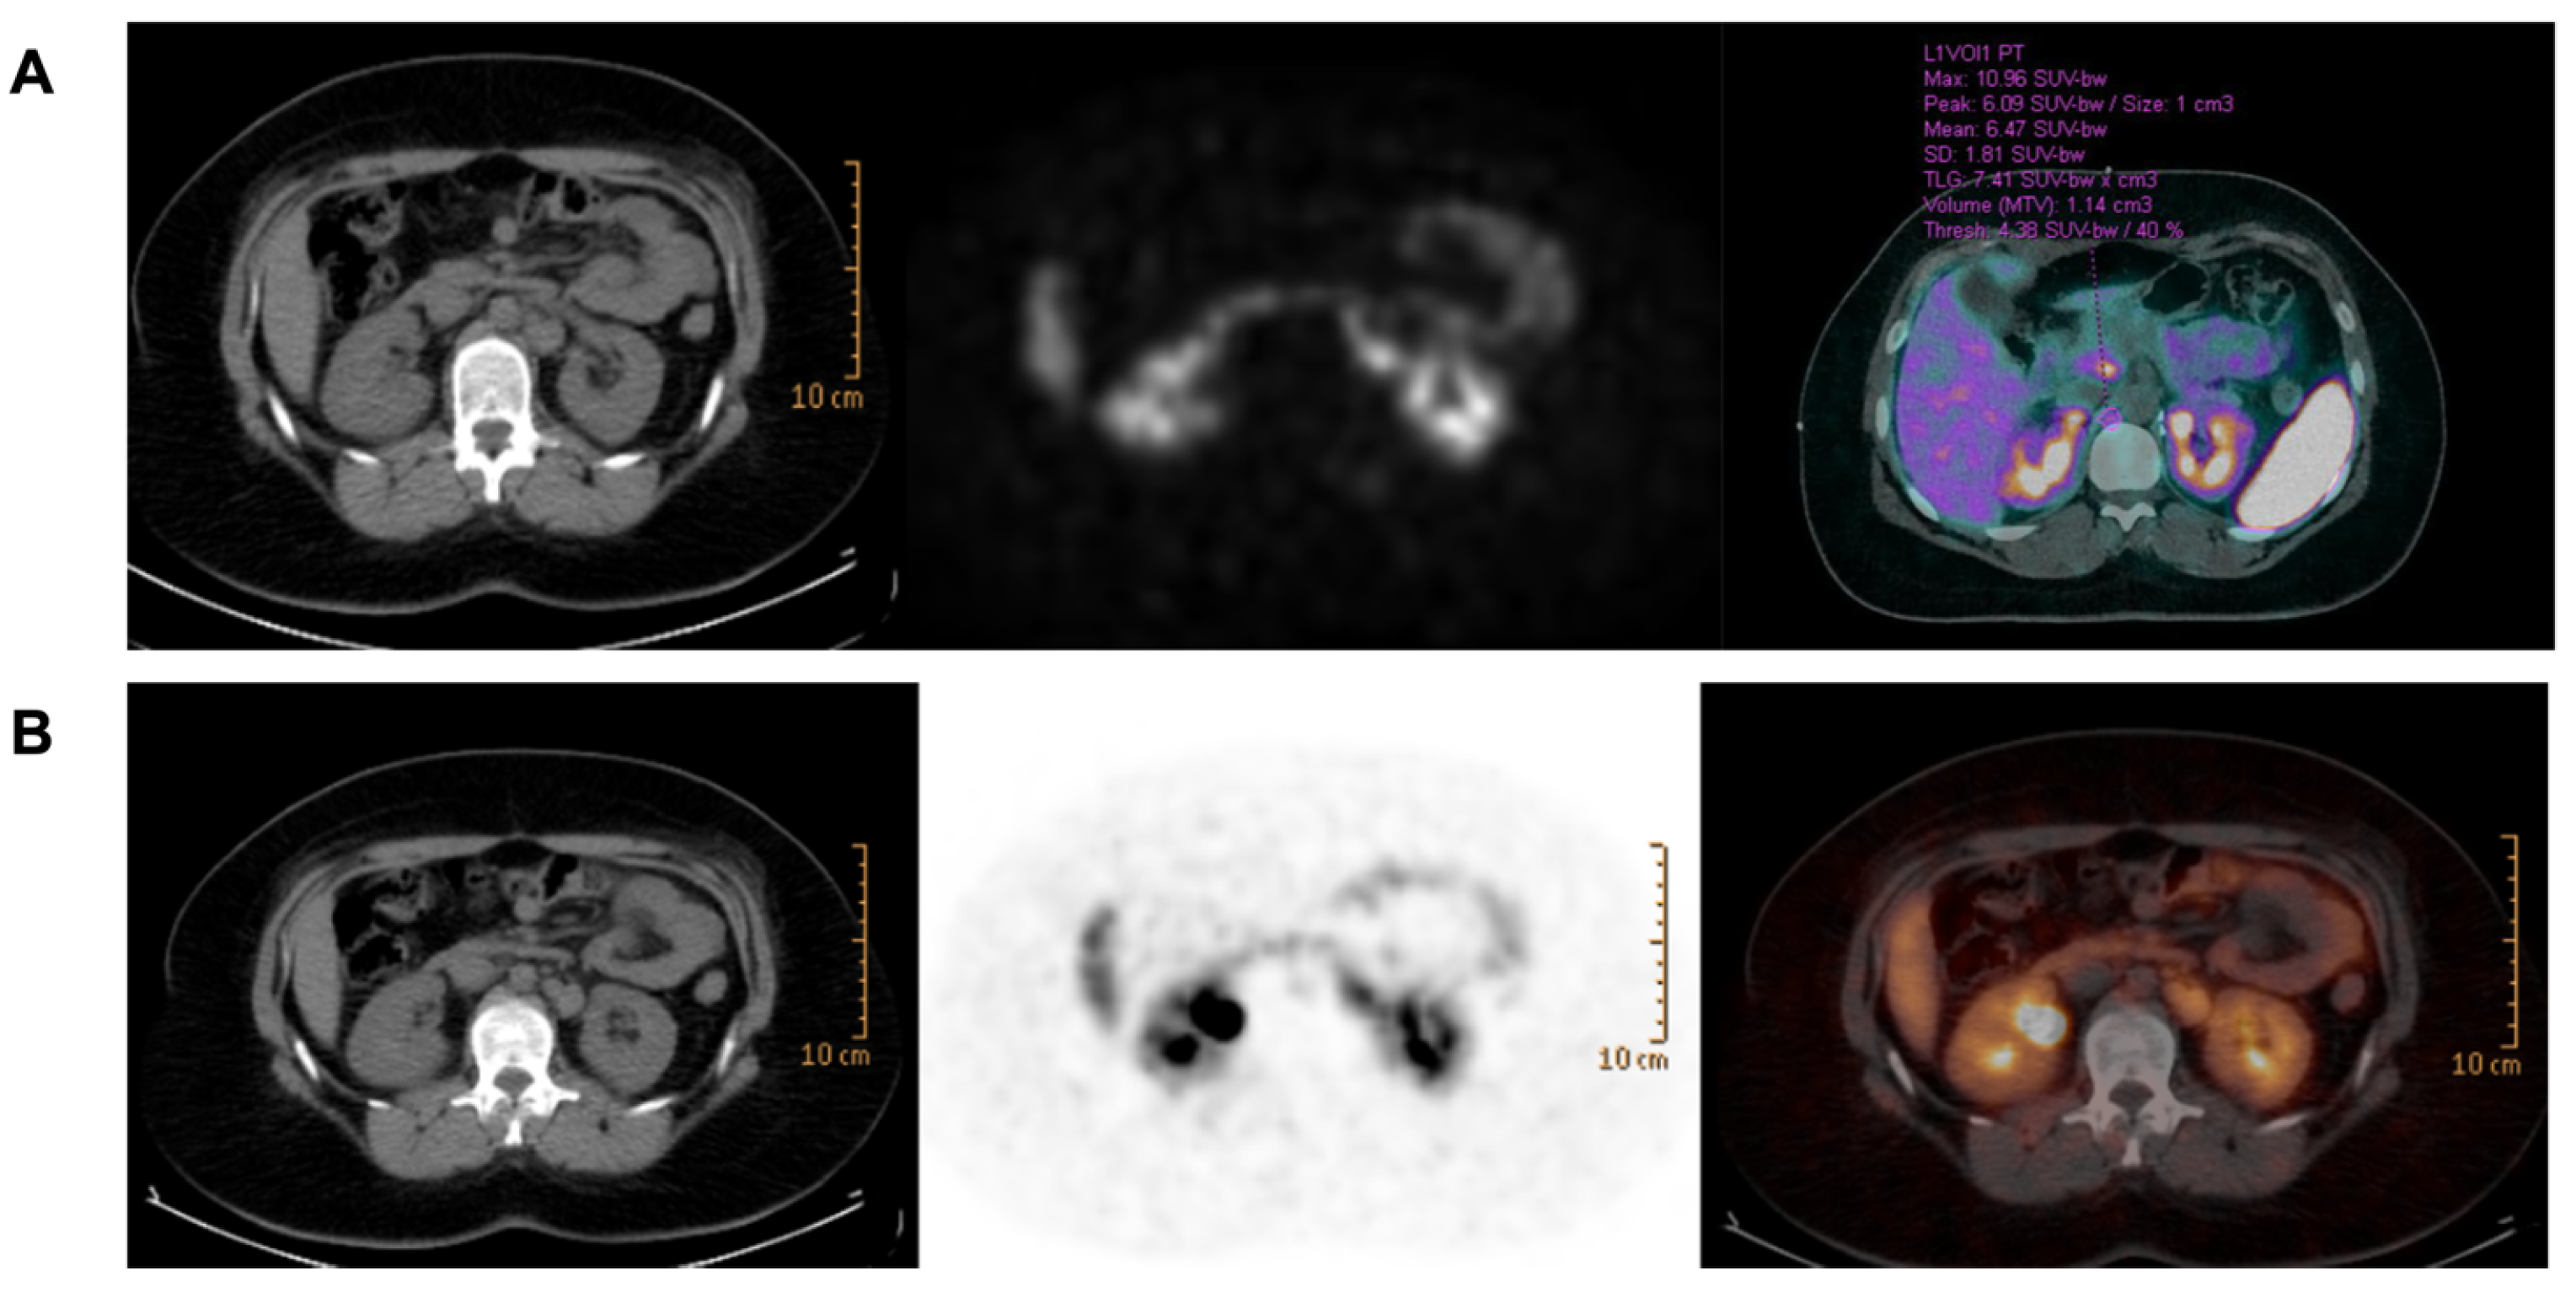

2.1. Case Presentation